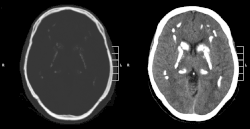

| CT scan of characteristic calcifications of the disease | |

Primary familial brain calcification[1] (PFBC), also known as familial idiopathic basal ganglia calcification (FIBGC) and Fahr's disease,[1] is a rare,[2] genetically dominant or recessive, inherited neurological disorder characterized by abnormal deposits of calcium in areas of the brain that control movement. Through the use of CT scans, calcifications are seen primarily in the basal ganglia and in other areas such as the cerebral cortex.[3]

Brain CT scan is the preferred method of localizing and assessing the extent of cerebral calcifications.